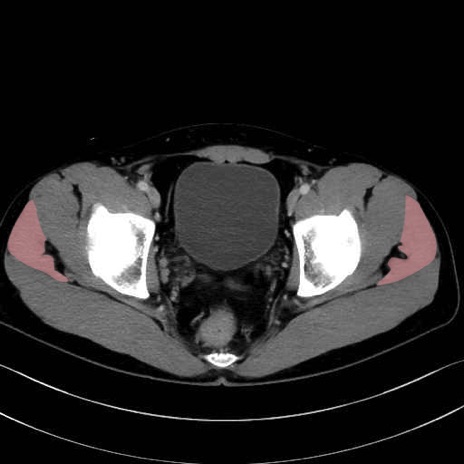

中殿筋 (Gluteus medius)